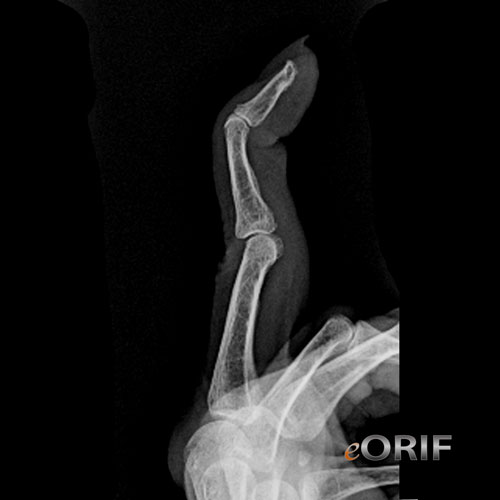

From eorif.com

Swan Neck Deformity M20.039 736.22 eORIF Mallet Finger Deformity Icd 9 Mallet finger is an injury to the extensor tendon that straightens the end joint of a finger or thumb, called the distal interphalangeal (dip) joint. See radiographs, ultrasound, and surgical techniques for. This code description may also have includes , excludes , notes,. Mallet finger injuries are named for the resulting flexion deformity of the fingertip, which resembles a mallet. Mallet Finger Deformity Icd 9.